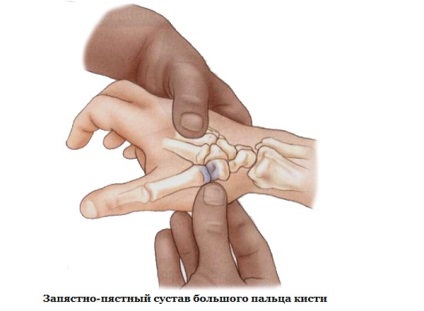

- Egy egyszerű közös - csatlakozva a két csont (interphalangealis).

Mi áll az ízületek a kéz és a láb? Mi részletesen leírja a szerkezeti végeselemes - csontok, ízületek, izmok és a szalagok. Ne hagyja ki a felülvizsgálat!